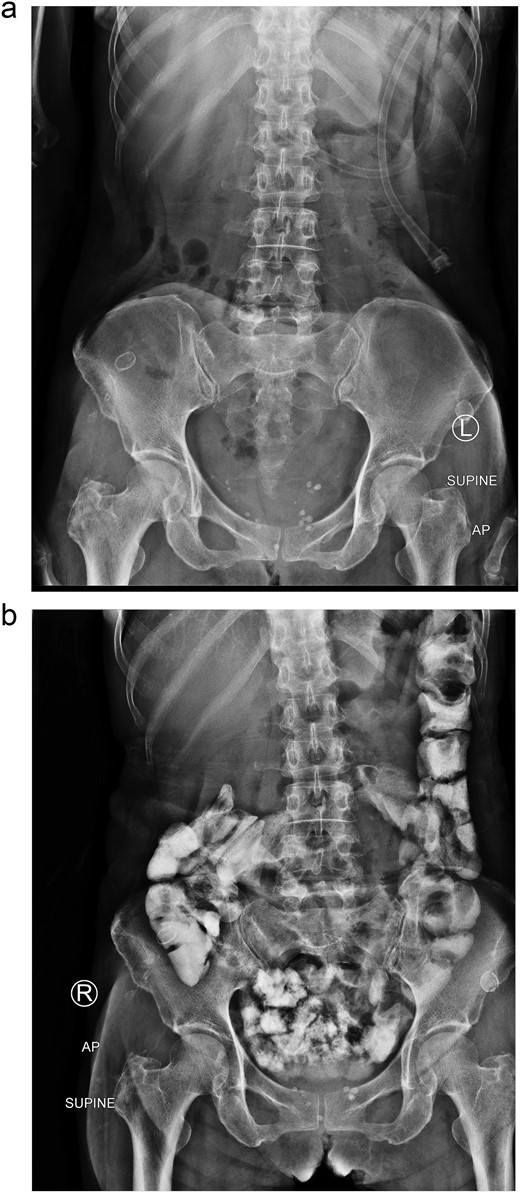

After 2 weeks of conservative treatment, the content from afferent limb decreased to 100–200 ml per day. Subsequently abdominal radiography showed collapsed stomach and normal bowel gas pattern. Oral contrast study revealed that contrast passed through small bowel and large bowel in 6 hours (Fig. 4). The patient was able to resume an oral diet and discharge at hospital admission Day 25th. On 3-mo follow-up, the patient could have solid food without any symptom.

Two weeks of conservative treatment: (a) abdominal plain film, (b) oral contrast study.